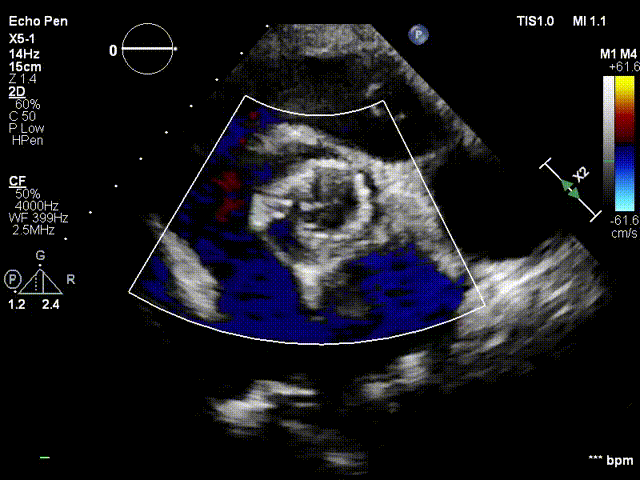

超声影像:

血流动力学改善,瓣膜形态良好,微量瓣周漏。